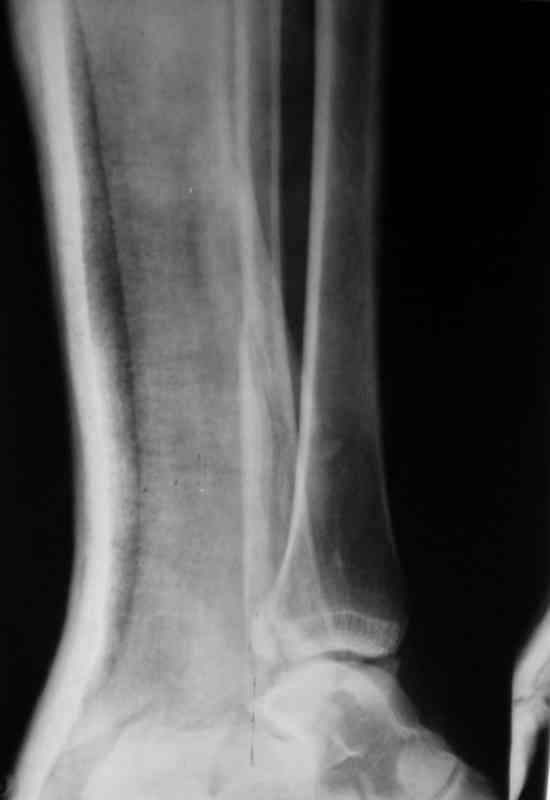

Перелом лодыжекКонтрольные рентгенограмы сделаны с нарушением укладок для стандартных проекций. Переделайте рентгенснимки и догда можно будет о чем-то иметь дискуcсию.

Рентгенограммы не сделаны в строго боковой и передне-задней проекциях.

Но и здесь видно, что внутренняя лодыжка "висит" - это говорит об интерпозиции. Выполняйте открытую репозицию и металлостеосинтез.

Можно сделать прямую с внутренней ротацией в 20 гр - еще лучше будет видно. Внутренняя лодыжка на боковом снимке не так уж плохо стоит. В любом случае - надо сделать нормальные снимки.

Вопрос к автору сообщения - эти лодыжки в задней гипсовой лонгете, судя по снимкам, или показалось?

Стандартными снимками считается прямая, боковая и мортиз!!!, а так трудно гадать, насколько потеря длины малоберцовой. На боковом снимке не сопоставленный перелом медиальной лодыжки и перелом заднего края без смещения.